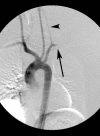

Background: Although relatively rare, blunt injury to thoracic great vessels is the second most common cause of trauma related death after head injury. Over the last twenty years, the paradigm for management of these devastating injuries has changed drastically. The goal of this review is to update the reader on current concepts of diagnosis and management of blunt thoracic vascular trauma.

Discussion: Blunt thoracic vascular injury remains highly lethal, with most victims dying prior to reaching a hospital. Those arriving in extremis require immediate intervention, which may include treatment of other associated life threatening injuries. More stable injuries can often be medically temporized in order to optimize definitive management. Endovascular techniques are being employed with increasing frequency and can often significantly simplify management in otherwise very complex patient scenarios.